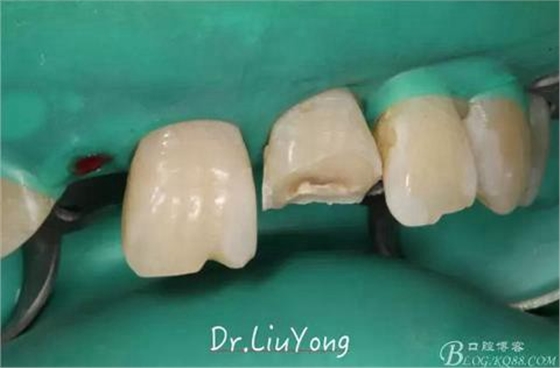

手術后1月,決定先行臨時修復,由于患者為重度深覆合,因此考慮將上前牙通過臨時修復體,降低切端的高度,減輕覆合,同時將舌傾的牙冠形態(tài)調(diào)整為較為直立。B2為根折到齦下1.5mm,考慮到患者無法接受正畸,同時如果近中鄰面行冠延長手術會帶來后續(xù)的黑三角美觀問題,因此選擇在橡皮障下行齦壁提升,然后A2纖維樁+樹脂核,A1-B2臨時樹脂貼面修復,A2臨時冠修復。